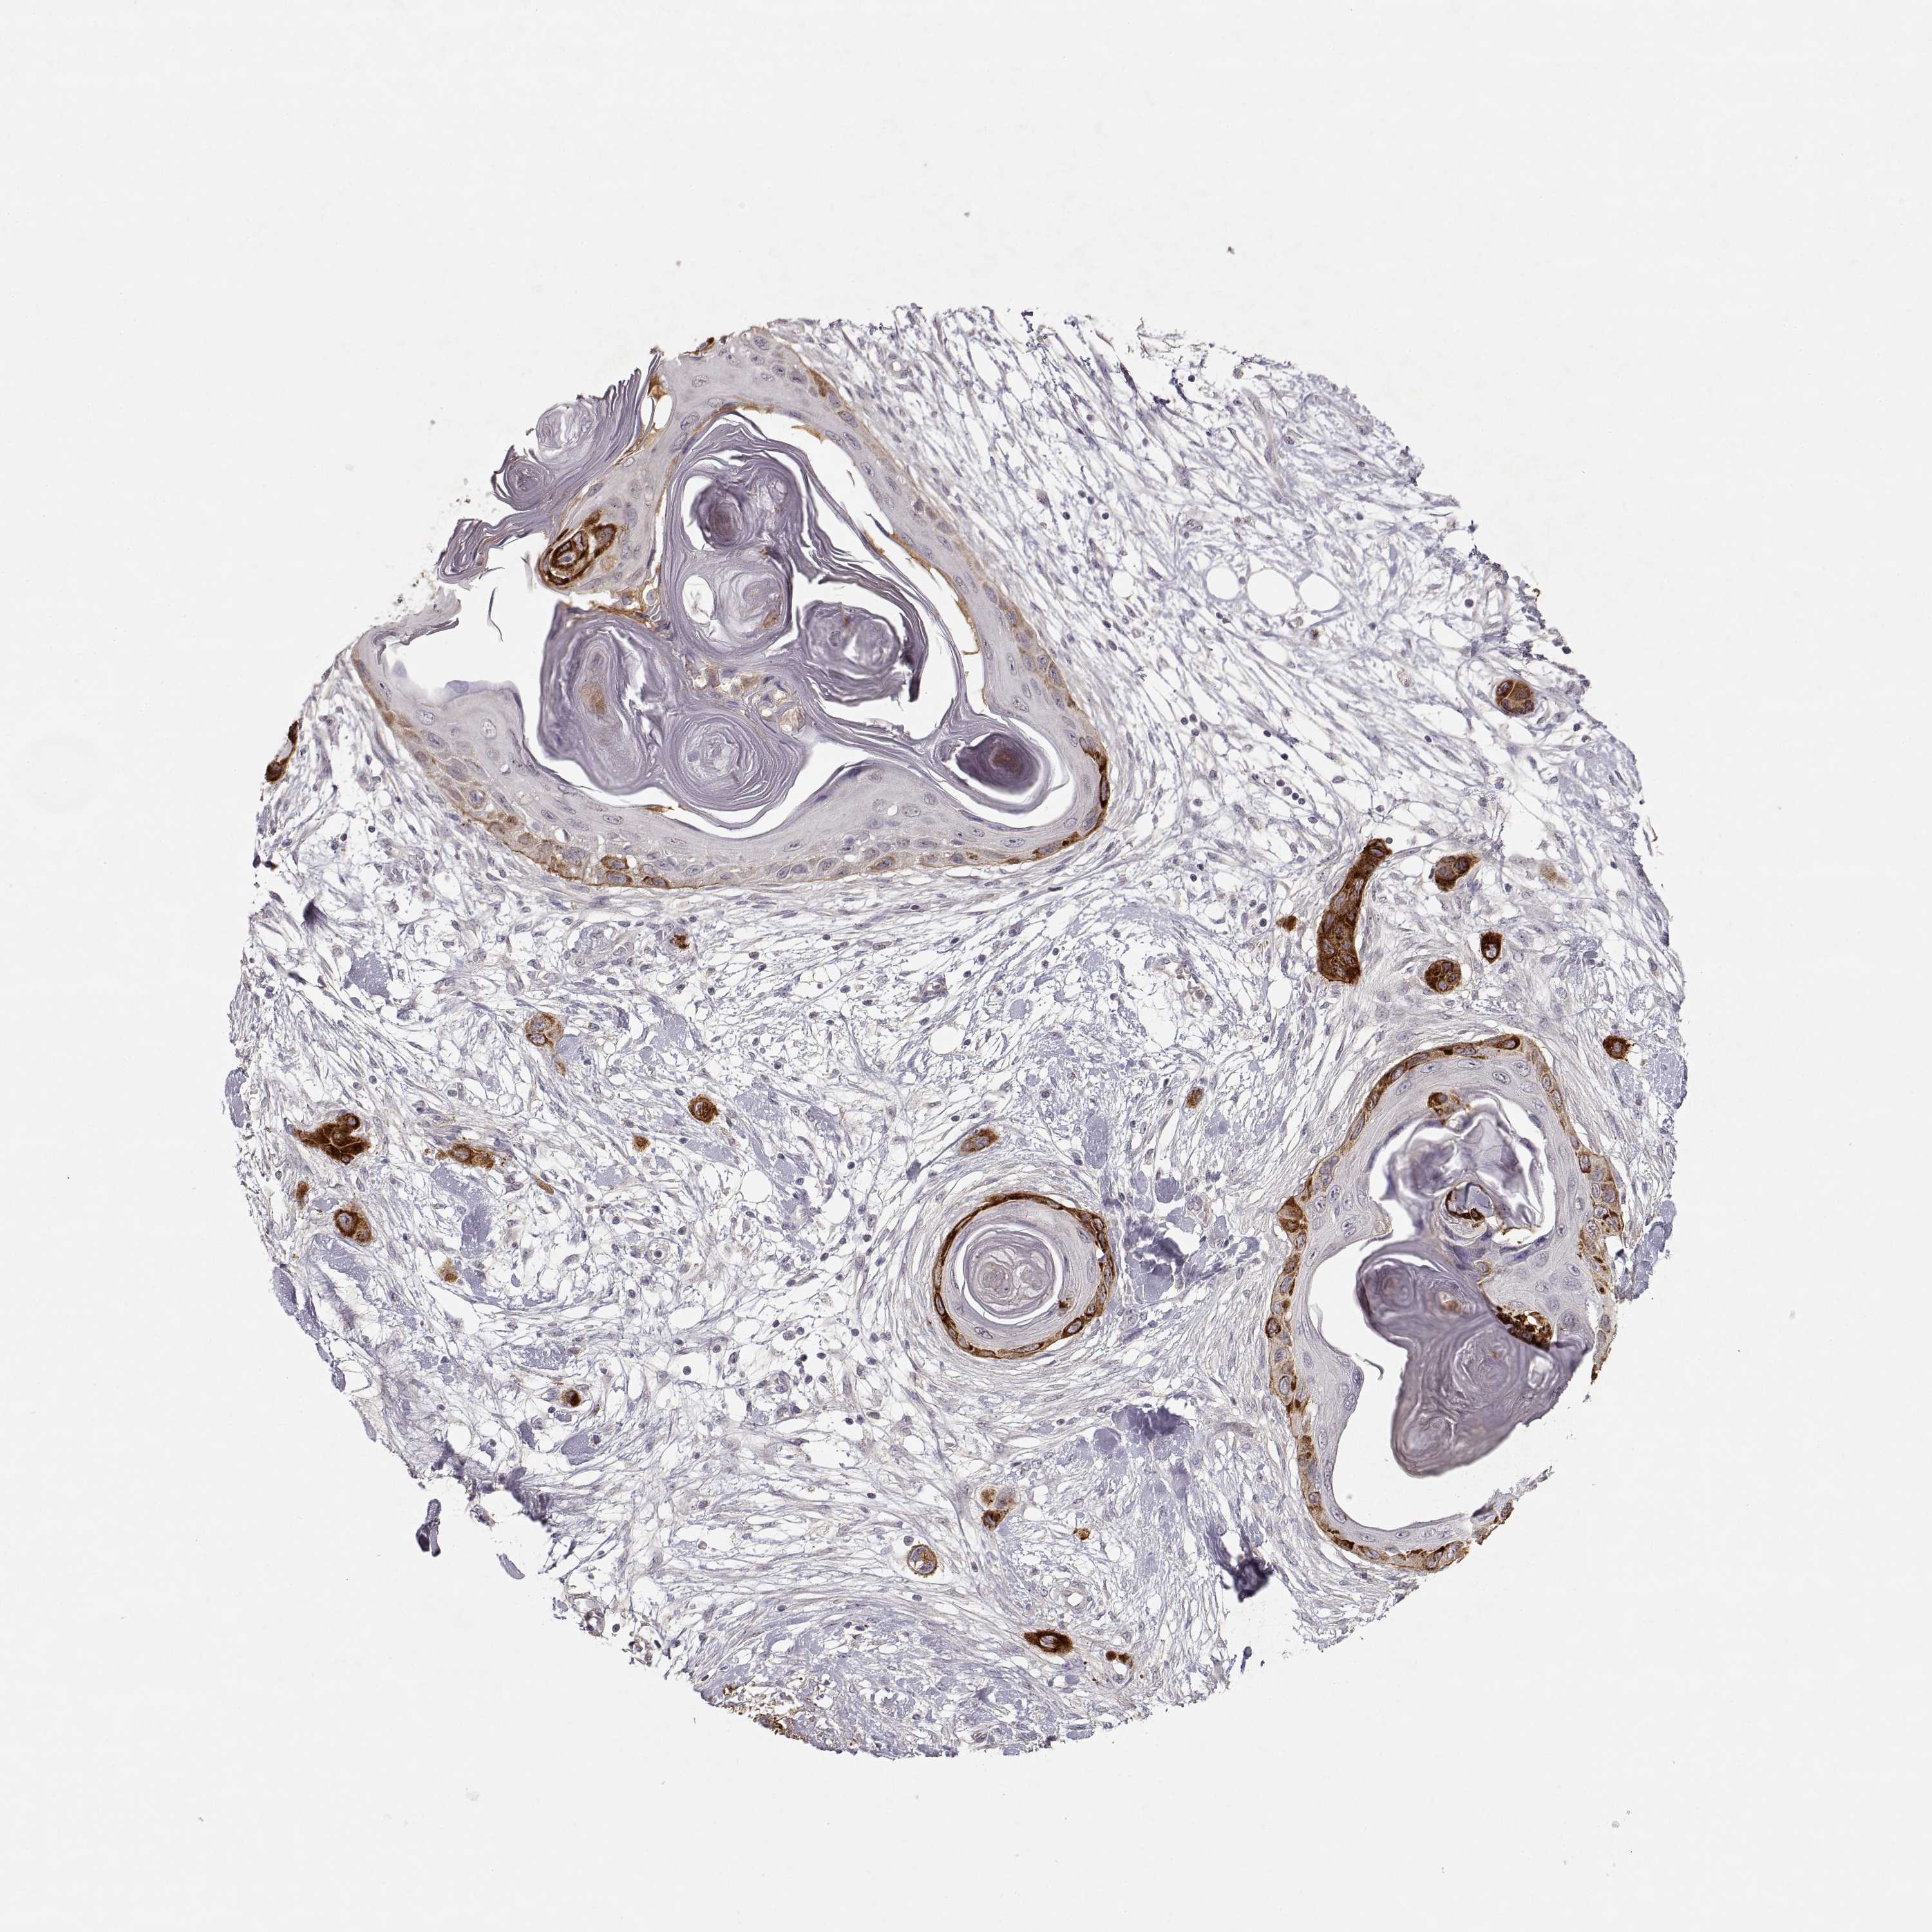

CANCER SKIN CANCER Show tissue menu

Basal cell and squamous cell cancer

SKIN CANCER - Protein expressioni

A mouse-over function shows sample information and annotation data. Click on an image to view it in a full screen mode. Samples can be filtered based on level of antibody staining by selecting one or several of the following categories: high, medium, low and not detected. The assay and annotation is described here.

Each image is clickable and will lead to virtual microscopy that enables deeper exploration of all samples and also displays staining intensity scores, fraction scores and subcellular localization as well as patient and tissue information for each sample.

Antibody CAB004257

Basal cell carcinoma